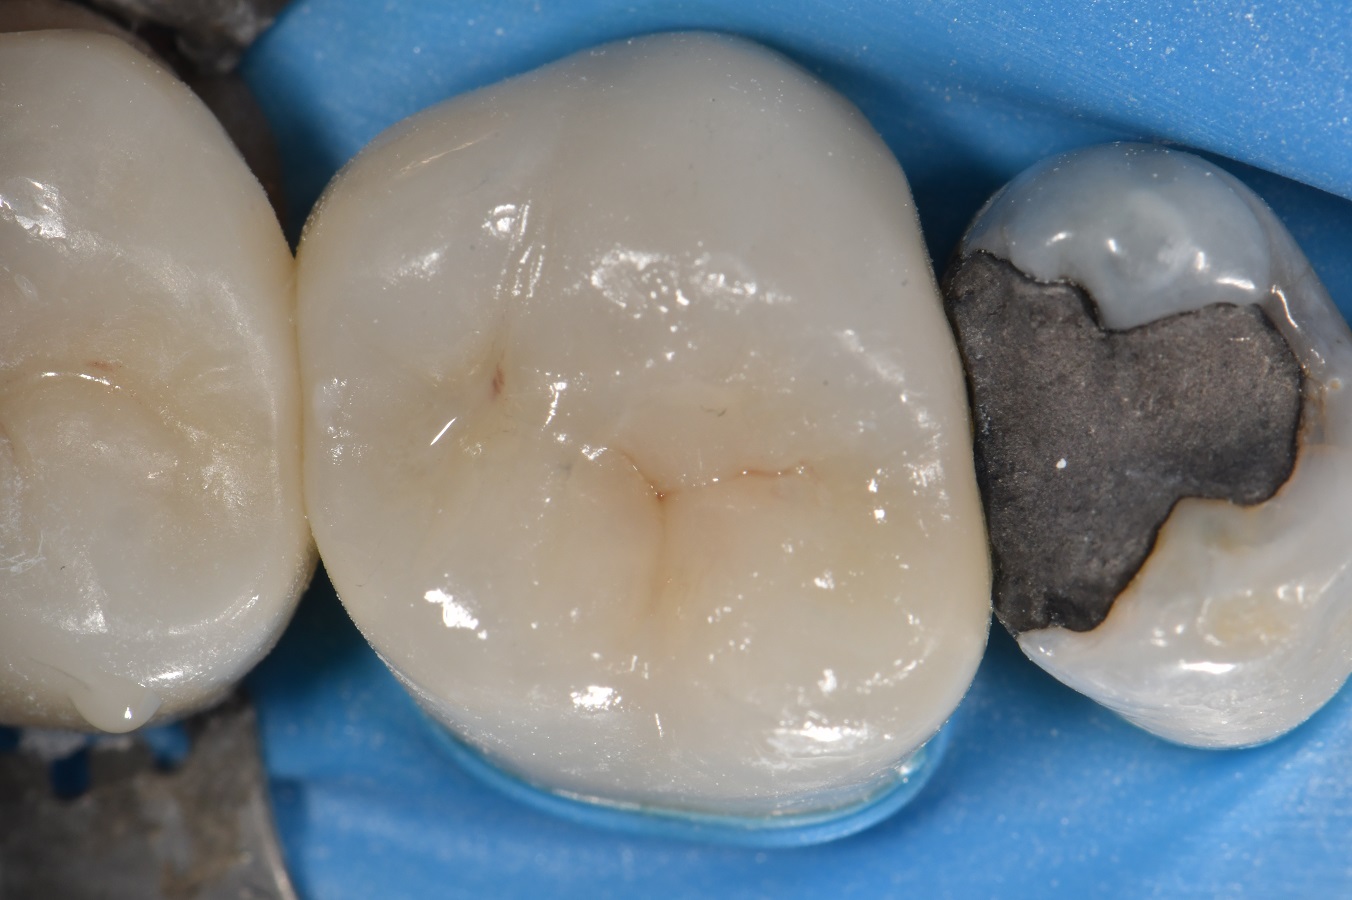

From www.theendoblog.com